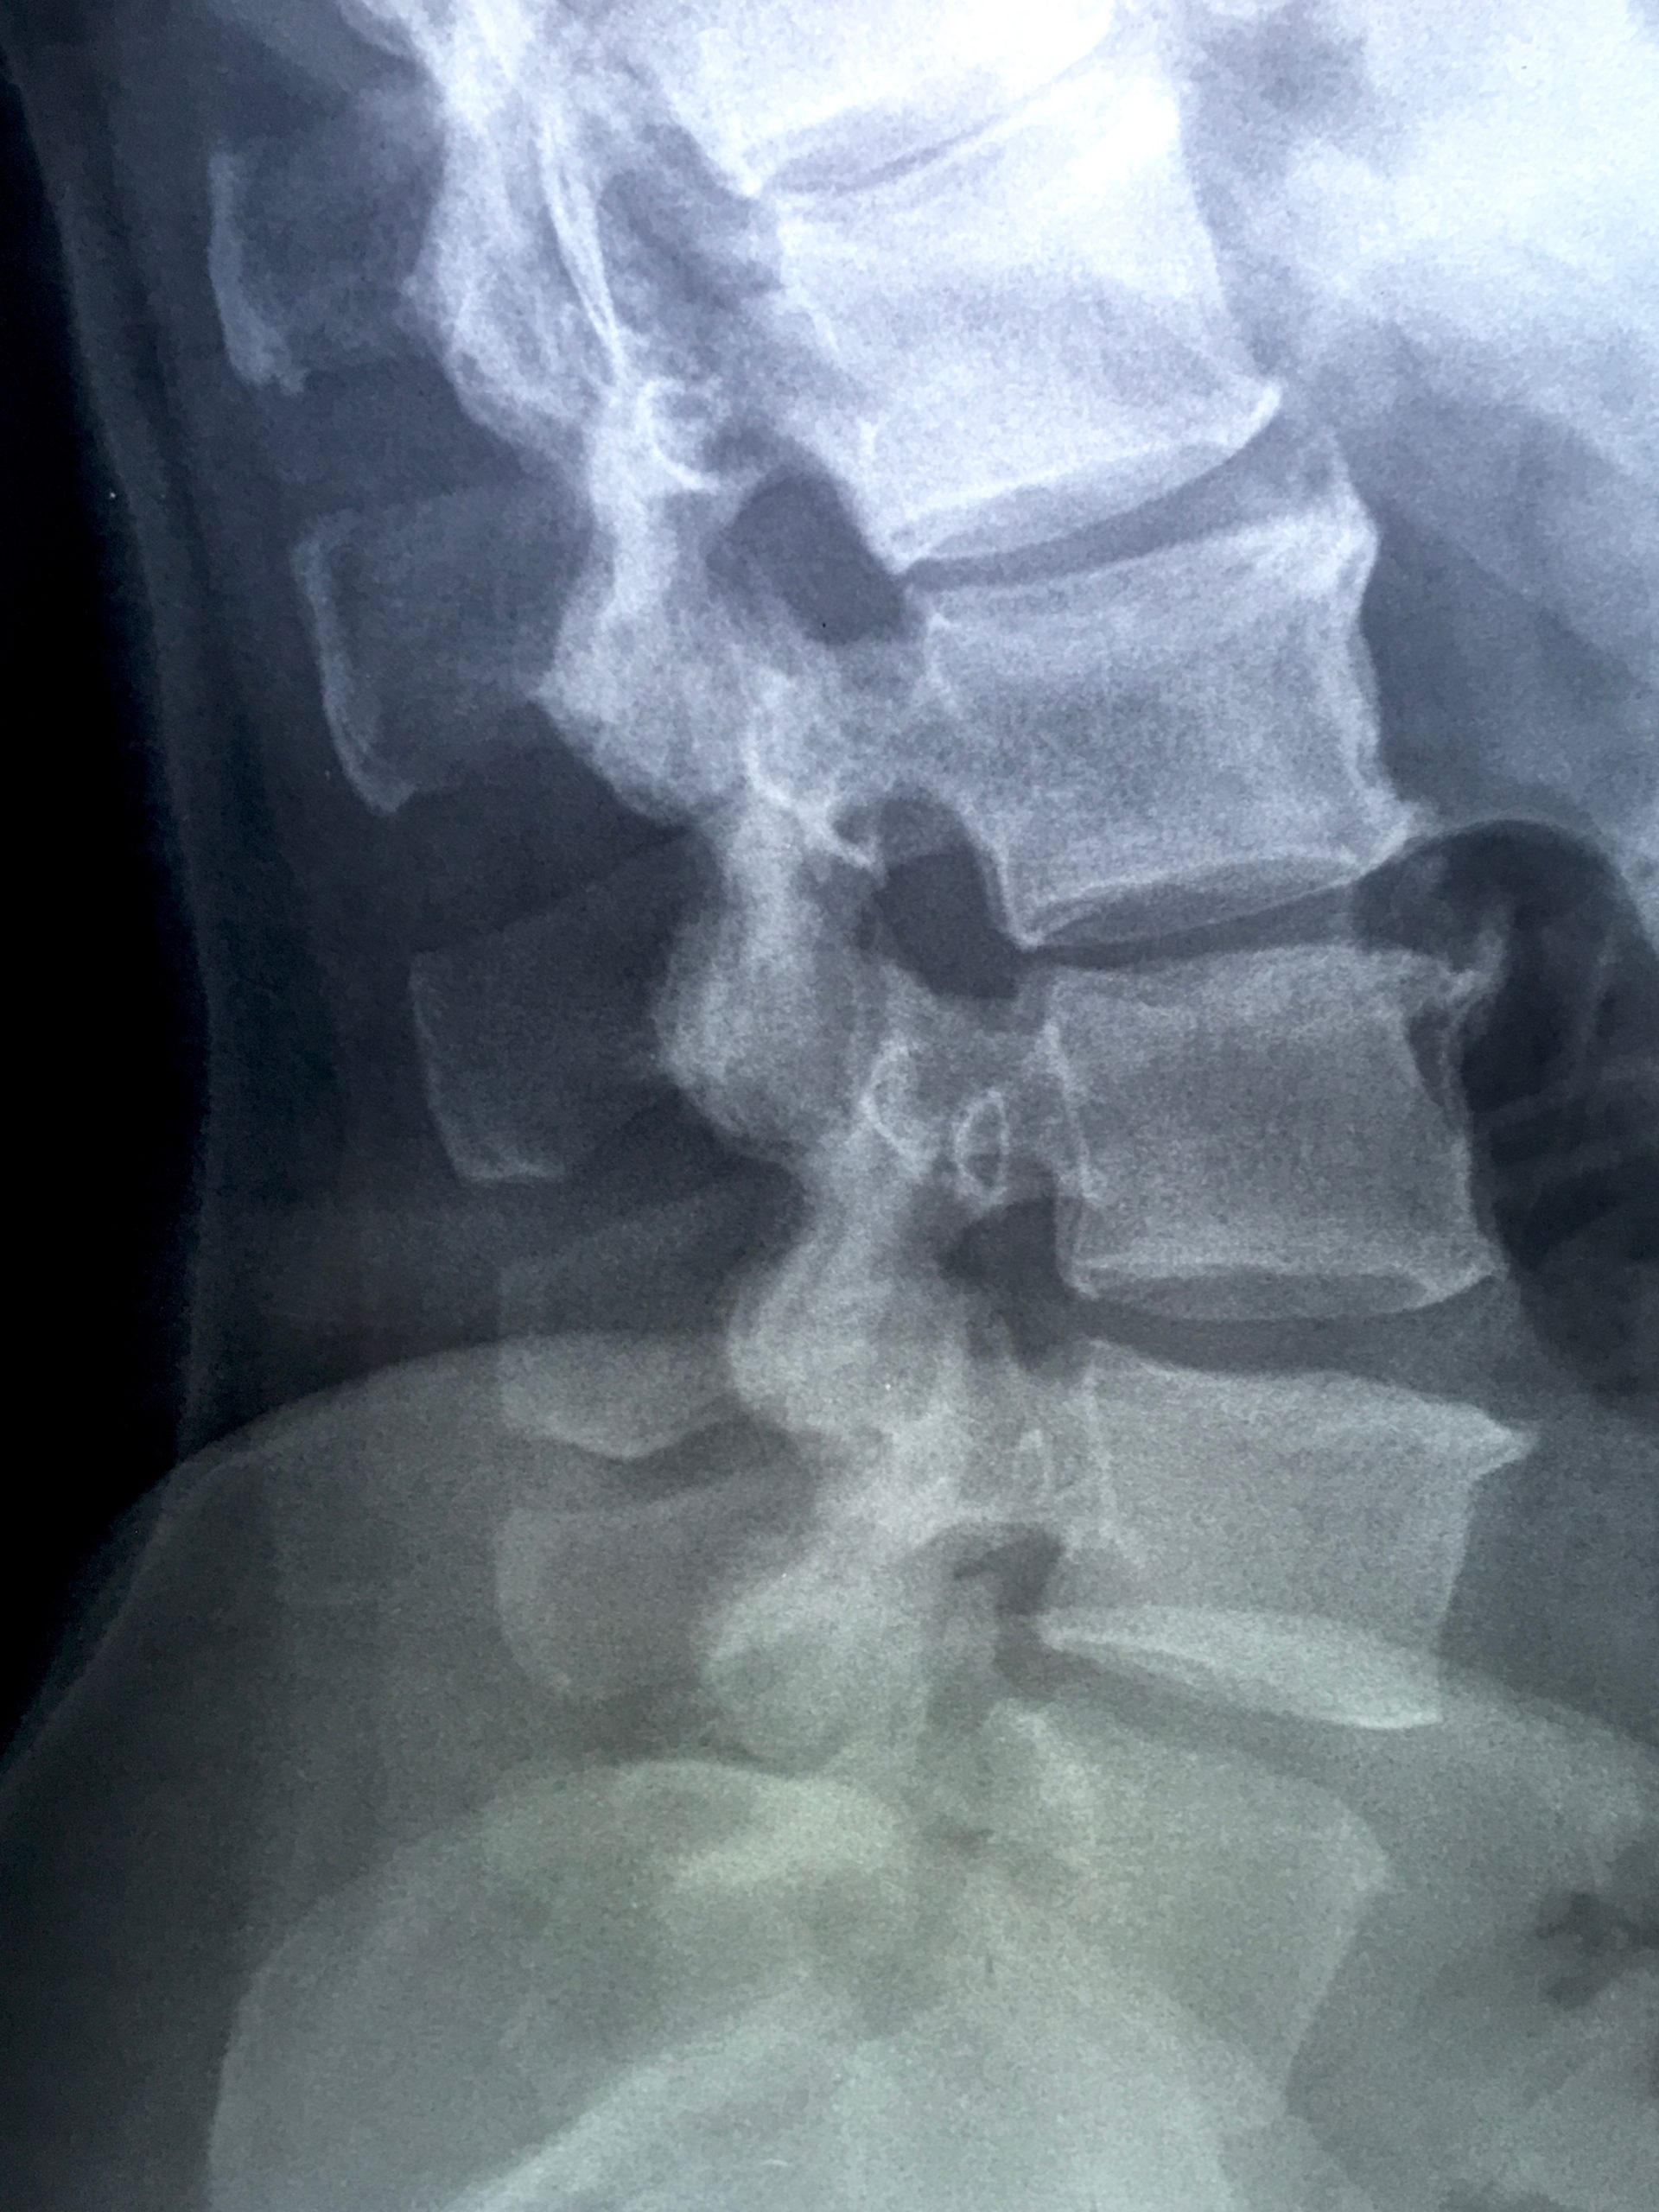

Scoliosis or a lateral curvature is not unusual, especially in women. When minimal, it often goes undiagnosed and unnoticed. However some people have a very pronounced and visible lateral spiral curve that disrupts structure and movement. This scoliotic spiralling pattern is NOT just about the spine – it is reflected throughout the ribs, the entire soft tissue container of the lungs and heart, and all surrounding musculature and fascias. The shoulders and pelvis are also affected in how they interface with the scoliotic torso. Whilst it may be impossible to unwind a complex scoliosis, it is possible to optimise structure and movement around it and through it, freducing pain and increasing mobility in the process.

• Disc Herniation

• Discectomy

• Laminectomy

• Spinal Fusions – Screws, Plates and Cages